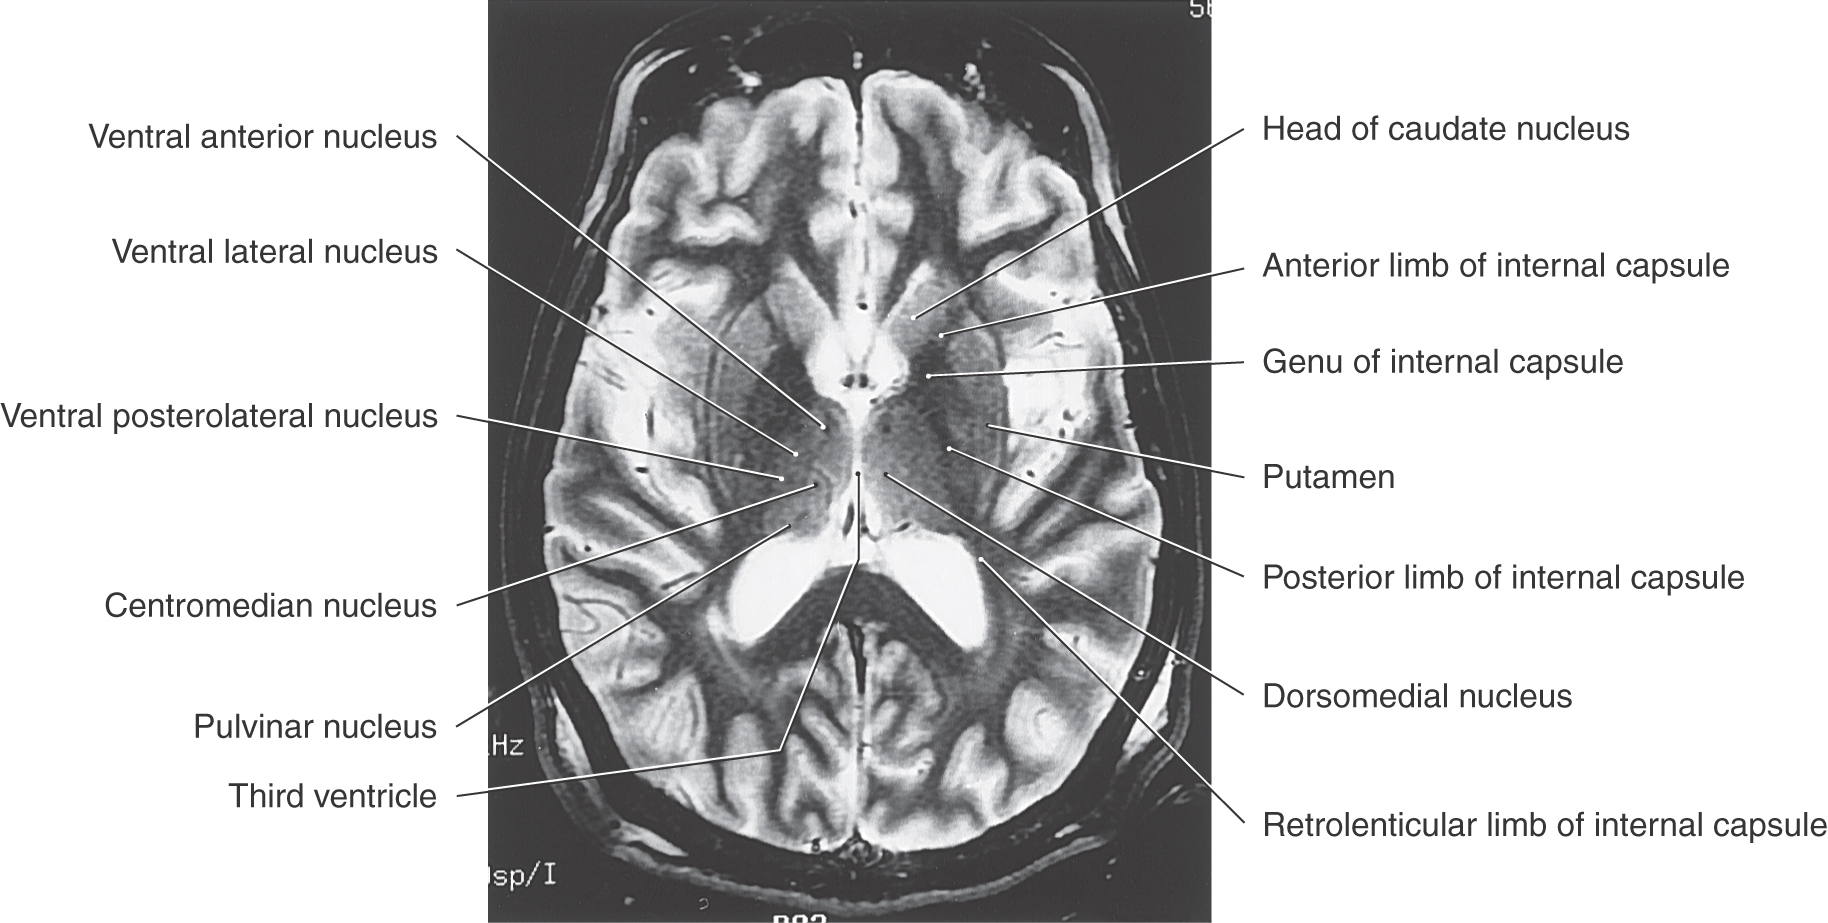

Figure 15-9. T2-weighted magnetic resonance image of the cerebral hemisphere in the axial plane. Emphasis in labeling is on diencephalic structures. Compare with Figure 15-12.

An internal medullary lamina, also consisting of myelinated fibers, extends into the substance of the thalamus, where it forms partitions or boundaries that divide the thalamus into its principal cell groups (Figs. 15-9 and 15-10): the anterior, medial, lateral, and intralaminar nuclear groups. The last cell group is located in the portion of the internal medullary lamina that separates the lateral and medial nuclear groups. In addition, there are midline thalamic nuclei located just superior to the hypothalamic sulcus.

The large ventral tier of the lateral group consists of three separate nuclei (Figs. 15-7, 15-8B, C, and 15-9). The ventral anterior nucleus (VA) and the slightly more caudal ventral lateral nucleus (VL) are important motor-related nuclei; the ventral posterior nucleus, consisting of ventral posterolateral (VPL) and ventral posteromedial (VPM) nuclei, convey somatosensory information to the cerebral cortex.

Embedded within the internal medullary lamina are the discontinuous groups of neurons that form the intralaminar nuclei. These cells are characterized by their projections to the neostriatum and to other thalamic nuclei, along with diffuse projections to the cerebral cortex. Two of the most prominent cell groups are the centromedian and parafascicular nuclei (Figs. 15-9 and 15-10). The centromedian nucleus projects to the neostriatum and to motor areas of the cerebral cortex, whereas the parafascicular nucleus projects to rostral and lateral areas of the frontal lobe. Other intralaminar nuclei receive input from ascending pain pathways and project to the somatosensory and parietal cortex.

Although the internal capsule is described in detail in Chapter 16, it is summarized here because of its important relationship to the thalamus. As seen in axial section (Fig. 15-12), the internal capsule consists of an anterior limb, genu, posterior limb, and retrolenticular limb. The genu is located immediately lateral to the anterior thalamic nucleus, at about the same level as the interventricular foramen. The anterior limb extends rostrolateral from the genu and is insinuated between the caudate and lenticular nuclei. The posterior limb extends caudolateral from the genu and separates the thalamus from the globus pallidus. As its name implies, the retrolenticular limb is the white matter located immediately caudal to the lenticular nucleus (Latin retro-, for “behind”).